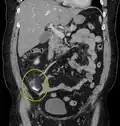

Appendicolith as seen on CT -